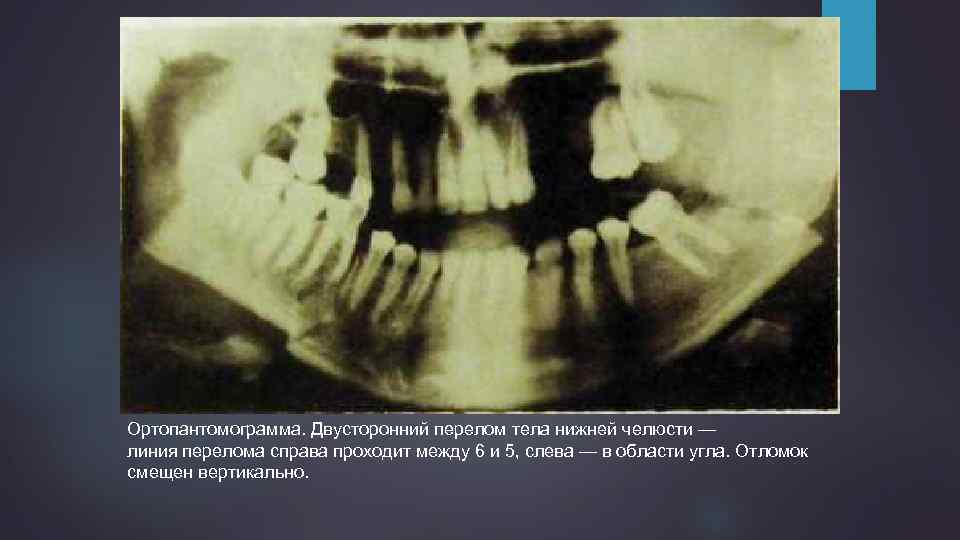

Ортопантомограмма. Двусторонний перелом тела нижней челюсти — линия перелома справа проходит между 6 и 5, слева — в области угла. Отломок смещен вертикально.